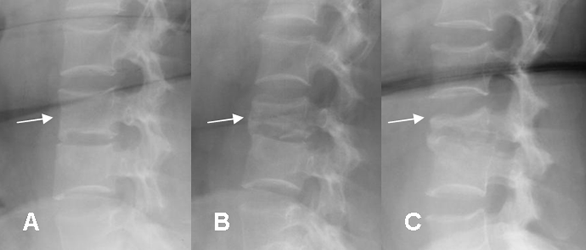

Fig 48. Osteomielitis TBC.

A: B: y C: Rx lateral. Progresión de osteomielitis. Inicialmente no se encuentran alteraciones. Después pérdida de altura en el cuerpo y disminución de la densidad. Finalmente secuelas, con un cuerpo denso y aplanado.